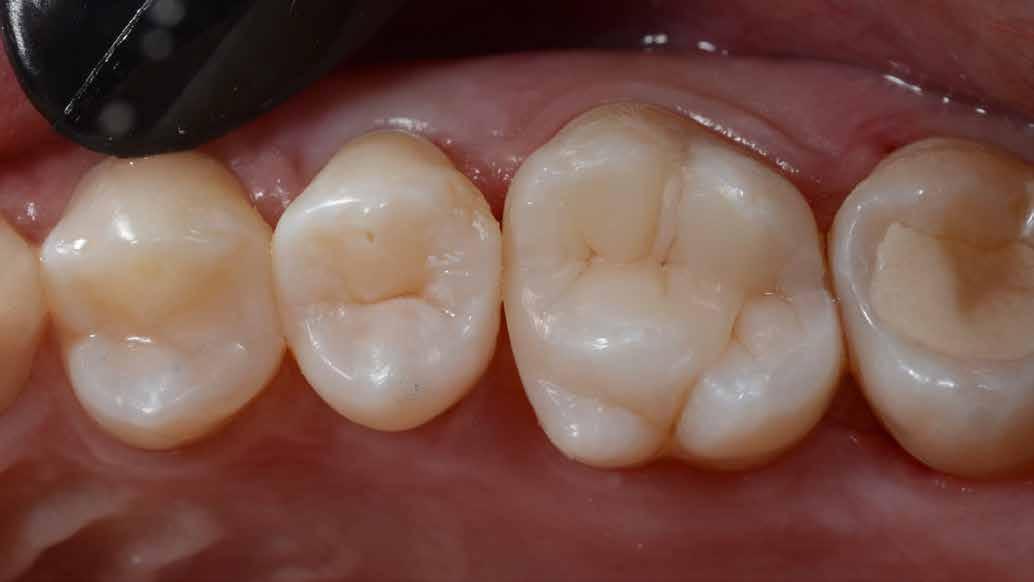

Az 53 éves hölgy páciens jobb felső 6-os fogában látható amalgámtömés cseréje volt a cél. A tömés mellett secunder caries és az amalgám következtében létrejött mesialis zárólécen áthaladó repedés, továbbá mesialis caries figyelhető meg (1. ábra). El kellett kerülni, hogy a tömés kifúrásakor az amalgámtörmelék a páciens szájába kerüljön, esetleg ebből valamennyit lenyeljen, a kezelés első lépésként kofferdám izoláció került fel a jobb felső kvadránsba (2. ábra). A kapocs a 1.7 fogra került, ezzel kényelmesen helyet teremtett a későbbiekben felkerülő matricarendszernek. Az egyszerre több fog izolálása lehetővé teszi, hogy a szomszédos fogak referenciául szolgáljanak a restauráció felépítése közben.

A régi amalgámtömés eltávolítását követően caries indikátor segítette a carieses laesio megfelelő kitisztítását a pulpa expozíciója nélkül. Ezután kerülhetett sor az ideális üregdesign kialakítására, továbbá a zománcszélek finírozására (3. ábra) Az approximális box megnyitása során az alátámasztatlan zománcprizmák eltávolításra kerültek, ezzel is csökkentve a secunder caries képződés veszélyét. Az így kialakuló forma elősegíti a matrica megfelelő adaptációját, végül pedig az approximális box határainak a hozzáférhetőségét, így finírozás során ez jobban kontrollálható és polírozható.

A Palodent V3 matricarendszer felhelyezését követően a zománc 10 másodperces szelektív savazása, majd lemosása és leszárítása után történt a kavítás bondozása Prime & Bond Universallal.

Kulcslépés: a II. osztályú üreget a matricarendszer segítségével I. osztályúvá lehetett átalakítani.

A pontosabb széli záródás érdekében célszerű a matrica illesztési határába némi folyékony kompozitot felvinni (NeoSpectra ST flow A2), majd megvilágítás nélkül a zárólécet paszta kompozittal (NeoSpectra STHV A2) felépíteni, miközben a kifolyó fölösleges folyékony kompozit eltávolításra kerülhet. Így ki lehetett használni és kombinálni a két különböző konzisztencia előnyeit.

A polimerizációt követően kerülhet sor a matricafeszítő gyűrű, valamint a matrica eltávolítására. A Palodent V3 fülekkel ellátott matrica kialakításának és a speciális PinTweezers csipesznek hála, a feszes kontaktpont ellenére a matrica könnyedén eltávolítható. Az éket viszont a kezelés végéig

célszerű bennhagyni, elkerülve egy esetleges nemkívánatos vérzést (4. ábra)

A matrica és gyűrű nélkül az approximális fal magassága, valamint a szomszédos fogakhoz viszonyítható dimenziók jobban megállapíthatóak. A jobb térlátás és a nagyobb mozgástér precízebb eredményhez vezet, csökkentve ezzel az utólagos finírozás mértékét, továbbá a részletgazdagon kialakított anatómiai struktúrák torzulásának az esélyét. Az üreg mélyebb részei SDR Plus A3-mal kerültek feltöltésre, majd NeoSpectra STLV A3-mal kiegészítve vált teljessé a dentin pótlása (5. ábra), ezzel létre lehetett hozni egy homorú formájú kromatikusabb alapot.

Ezt követően csücsökről csücsökre haladva a felső hatosokra jellemző anatómiai struktúrák, megfelelő orientációval bíró csücsöklejtők és elsődleges barázdák Neo Spectra

HV A2 anyagból kerültek kialakításra (6. ábra). Apró „kompozit-hurkákkal” kiegészítve létrehozható a csücskökön belüli tagoltság, ezzel kialakítva a másodlagos barázdarendszert és egy sokkal kidolgozottabb anatómiai struktúrát (7. ábra). A fogorvos esetleges „művészi hajlamát” is figyelembe véve, a természethű megjelenés barázdafestéssel (Micerium - Stain Brown 2) még tökéletesebb lehet (8. ábra). Ezzel a korábban részletgazdagon kialakított ba-

rázdarendszer kiemelhető, és optikailag fokozható a gödröcskék mélysége is.

A restauráció megfelelő polimerizációja után célszerű a kofferdám nyújtotta retrakciót kihasználni, és a restauráció széli záródásában levő esetleges kompozitfölösleg elfinírozását jobb rálátás mellett elvégezni (9. ábra). Ebben nagy segítségünkre lehet az Enhance rendszer, mely a kompozitot nagyon szépen elsimítja, de a természetes fogszövetet nem bántja.

A matricázott terület széli záródásának a kidolgozásában az EVA polírozó (10. ábra) lehet a segítségünkre, amellyel a gingiva sérülése megelőzhető, és a kialakított feszes kontaktpont sem kerül redukcióra (11-12. ábra)

A kofferdam eltávolítását követően kerülhetett sor az occlusio beállítására csücsöklejtők domborúságának a redukciója révén (13. ábra). A harapás gyémántfúrókkal történő beállítása után a polírozás Enhance rendszerrel történt, melynek végső lépéseként a PrismaGloss használatával (14. ábra) nyerhette el a restauráció a végső fényességét (15. ábra)

A ma rendelkezésre álló modern eszközöknek és anyagoknak hála II. osztályú üregek direkt módon kiszámíthatóan restaurálhatóak. A matricarendszernek köszönhetően helyreállítható a feszes kontaktpont, a „kaméleon effektussal” bíró kompozit pedig a tömés integrációjáért felel. A megfelelő adhézió, a precízen kidolgozott széli záródás és a plakkréteg megtapadását nehezítő polírozott felszín a kezelés hosszú távú sikerének a garanciája. Mindezek együtt egy hosszú távon tartós, funkcionális és esztétikai rehabilitálást tesznek lehetővé.